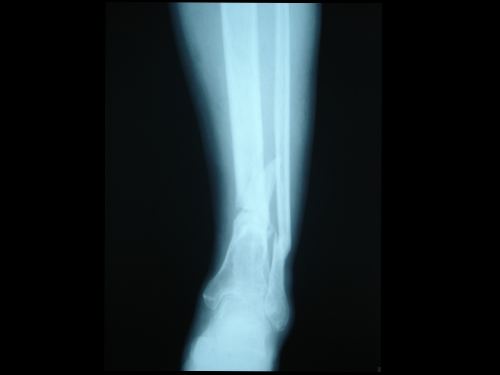

脛腓骨骨折

脛腓骨骨干骨折在全身骨折中最為常見。10歲以下兒童尤為多見。其中以脛骨干單骨折最多,脛腓骨干雙折次之,腓骨干單骨折最少。脛骨是連接股骨下方的支承體重的主要骨骼,腓骨是附連小腿肌肉的重要骨骼,并承擔(dān)1/6的承重。脛骨中下1/3處易于骨折。脛骨上1/3骨折移位,易壓迫腘動(dòng)脈,造成小腿下段嚴(yán)重缺血壞死。脛骨中1/3骨折淤血潴留在小腿的骨筋膜室,增加室內(nèi)壓力造成缺血性肌攣縮。脛骨中下1/3骨折使滋養(yǎng)動(dòng)脈斷裂,易引起骨折 延遲愈合。